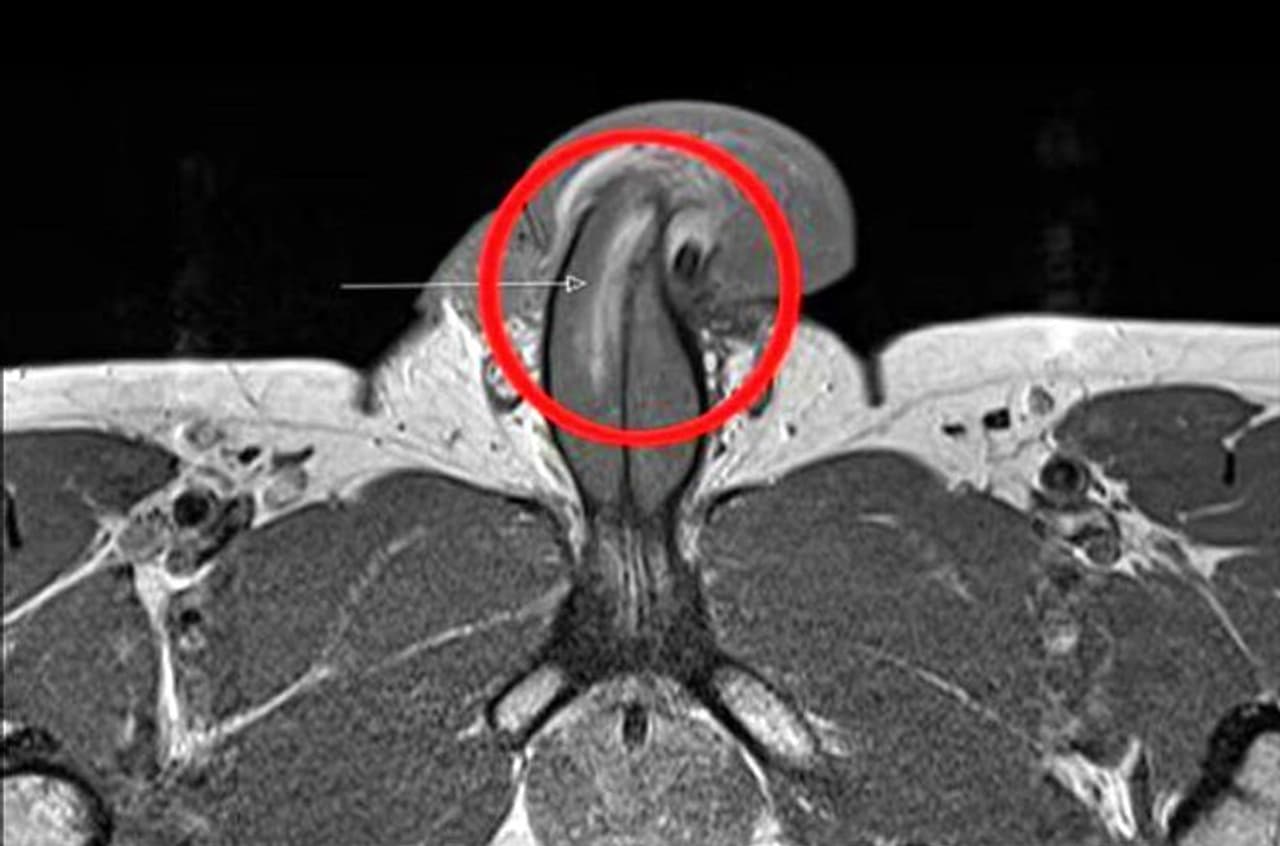

BMJ-তে প্রকাশিত ওই ব্যক্তির পুরুষাঙ্গের MRI স্ক্যান , যাতে ধরা পড়ে ৩ সেমি দীর্ঘ 'টিয়ার'-টি

এমআরআই (MRI) স্ক্যান করে ডাক্তাররা দেখেছিলেন, ওই লোকটির পুরুষাঙ্গের ডানদিকে উল্লম্বভাবে তিন সেন্টিমিটার দীর্ঘ টিয়ার রয়েছে। তবে, ওই আঘাতের ছয় মাসের মধ্যেই ফের সহবাস শুরু করতে সক্ষম হয়েছিলেন ওই ব্যক্তি। এমমনটাই জানা গিয়েছে বিএমজে থেকে। শুধু তাই নয়, আঘাতের কারণে তার যৌন জীবন এতটুকু ক্ষতিগ্রস্তও হয়নি।